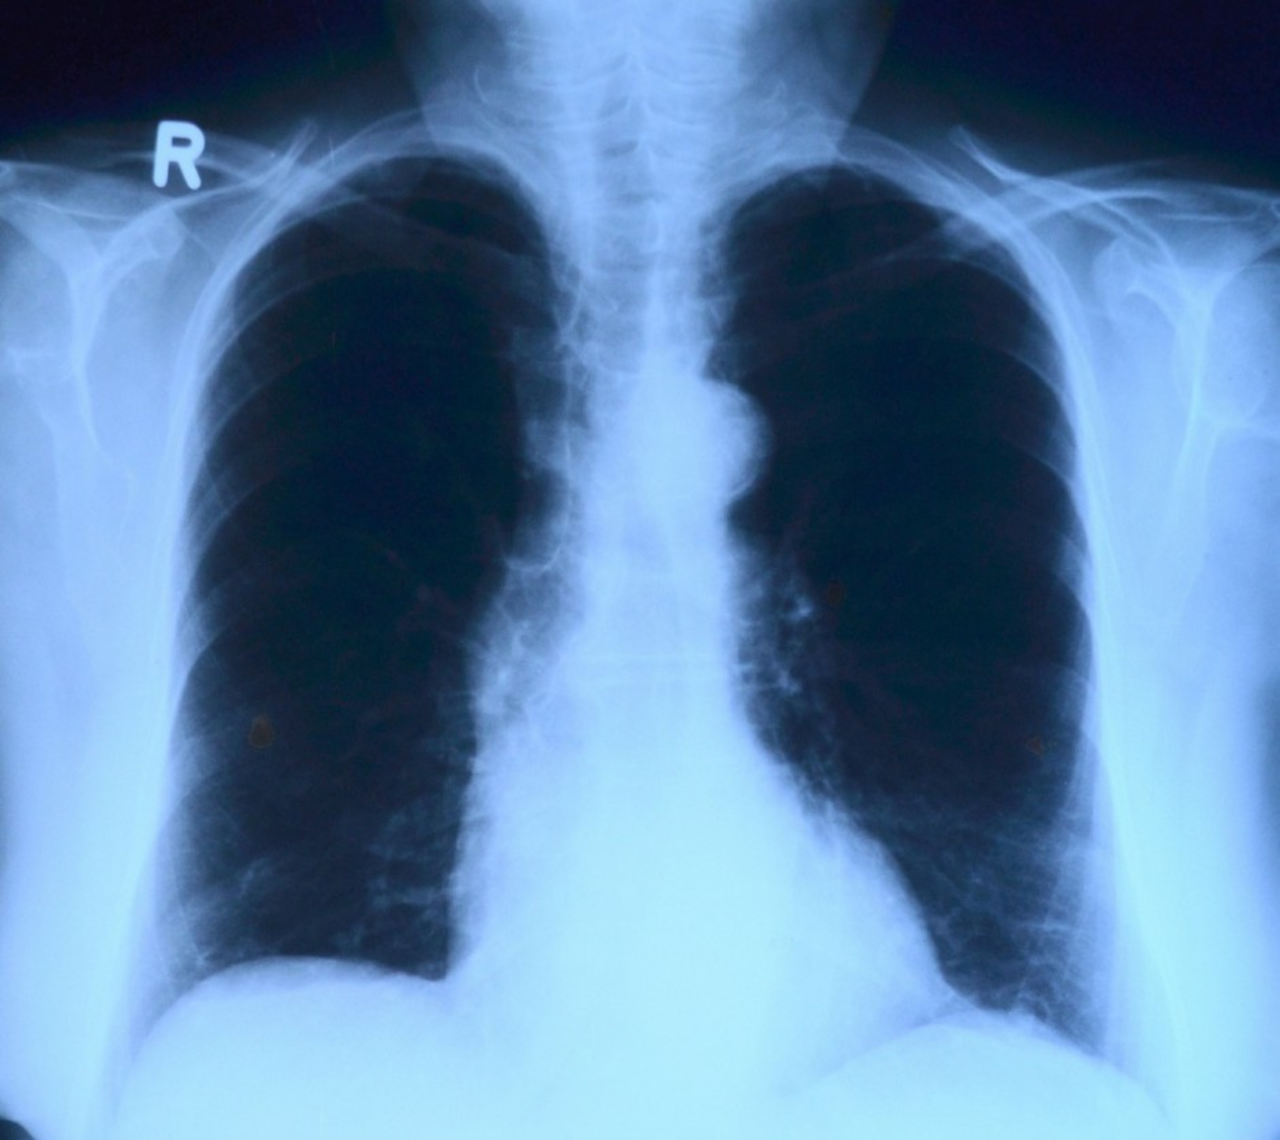

Większość osób przechodzi zakażenie koronawirusem łagodnie lub nawet bezobjawowo. Jednak nawet kilka miesięcy po przebytej infekcji niektórzy mogą zmagać się z szeregiem powikłań, wśród nich jest m.in. uszkodzenie miąższu płuc, schorzenia nerek, wątroby, zmiany skórne czy powikłania w obrębie układu sercowo-naczyniowego.

Jak podkreśla dr n.med. Zbigniew Bajor, pulmonolog i alergolog coraz więcej osób po przebytej chorobie Covid-19 udaje się do specjalistów aby skontrolować stan swojego zdrowia i wykonać badania, np. prześwietlenie płuc. – Naturalny przebieg tego schorzenia, nie jest do końca poznany, dużo już wiemy o drodze szerzenia się tego patogenu, o jego diagnostyce, coraz więcej o metodach leczenia, natomiast jeśli chodzi o następstwa – szczególnie te odległe – jest  dużo niewiadomych, o których dowiemy się z czasem. – Najczęstszym powikłaniem, które możemy zaobserwować jest uszkodzenie miąższu puc, spowodowane nadmierną odpowiedzią układu immunologicznego. Spotykam się z często z młodymi pacjentami, którzy czynnie uprawiali sport, mieli bardzo dobrą wydolność oddechową, a problemy płucne utrzymują się u nich nawet kilka miesięcy od zakażenia. Istnieją też powikłania ze strony układu sercowo-naczyniowego, nerek, wątroby, mogą również wystąpić zmiany skórne oraz zaburzenia psychiczne czy osłabienie koncentracji – wymienia specjalista.

Jak podkreśla lekarz około 80 procent osób przechodzi chorobę Covid-19 łagodnie, natomiast pozostałe odczuwają większe dolegliwości i to u nich najczęściej występują powikłania, chodź nie jest to reguła. – Powikłania dotykają często osób ze schorzeniami przewlekłymi, czy to ze stronu układu oddechowego np. z ciężką astmą oskrzelową i  przewlekłą obturacyją chorobą płuc czy ze strony układu sercowo-naczyniowego. Są też osoby zdrowe, u których po przebyciu choroby i okresie stabilizacji następuje nasilenie pewnych dolegliwości, np. ogólne osłabienie organizmu czy duszności –mówi dr n.med. Zbigniew Bajor.

Infekcja Sars-Cov-2 nawet o lekkim przebiegu może prowadzić również m.in. do zapalenia mięśnia sercowego, ponadto specjaliści obserwują wzrost ryzyka zawału serca oraz zaburzenia jego rytmu. Do poważnych zagrożeń związanych z zakażeniem koronawirusem należą również powikłania zakrzepowo-zatorowe.